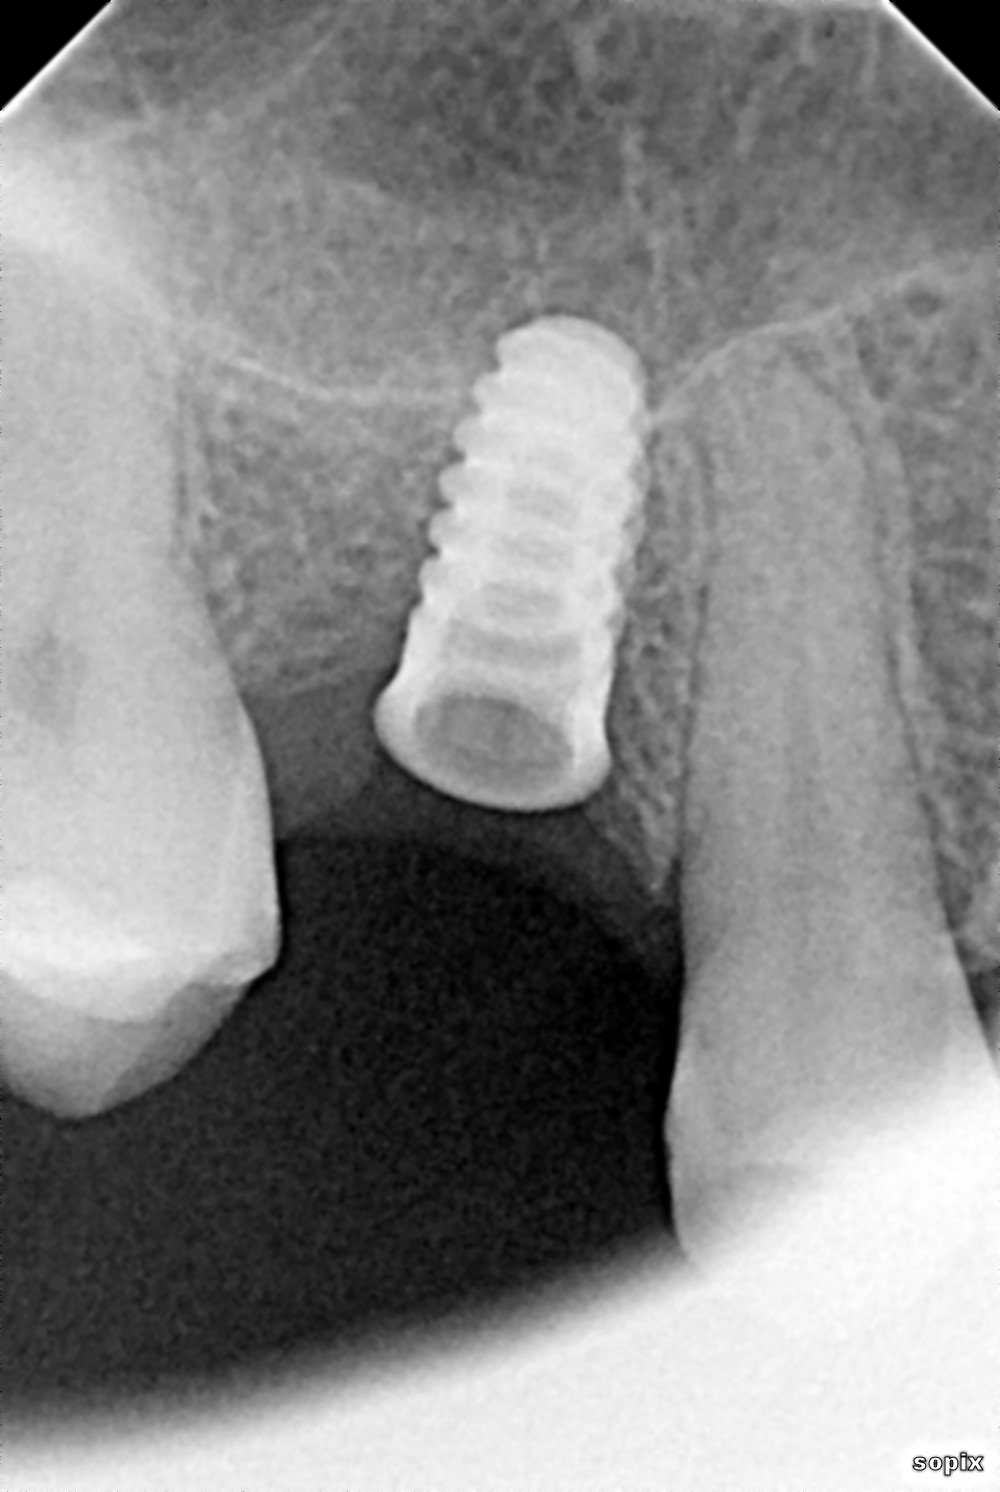

La paciente acude a consulta para rehabilitar el implante de la rx periapical. Es de conexión externa a hexágono. Creo que se puso en un FunnyDent. ¿Alguien podría reconocerlo o [...]

Impalnte en pieza 24 (con corona puesta en la radiografía y foto de conexion). Tendrá como 20-30 años